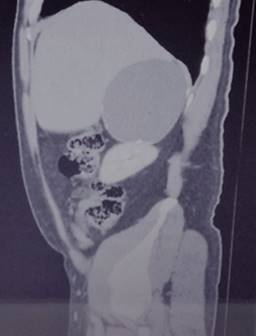

Biometría hemática, pruebas de función hepática, renales, TP y TPT de mayo de 2018 normales. No se realiza cortisol, aldosterona, catecolaminas urinarias ni metanefrinas. Tomografía de mayo reporta en glándula suprarrenal derecha imagen hipodensa con diámetros máximos de 101 mm, calcificaciones en su interior con efecto ocupativo y compresivo sobre las estructuras vecinas (Figuras 3 a 6). Completándose su valoración preoperatoria por medicina interna, se programa abordaje quirúrgico anterior abierto y bajo profilaxis antibiótica con ceftriaxona 2 g en dosis única, se realiza incisión subcostal derecha, destechamiento con electrocauterio de quiste suprarrenal derecho de 10 × 9 cm, con adherencias al hígado, contenido de aproximadamente 400 ml de líquido hialino y calcificaciones de alrededor de 20 × 40 mm en su interior. Se coloca drenaje abierto, penrose de ½” (19 mm) en espacio subfrénico ante la sospecha de hemorragia postoperatoria.